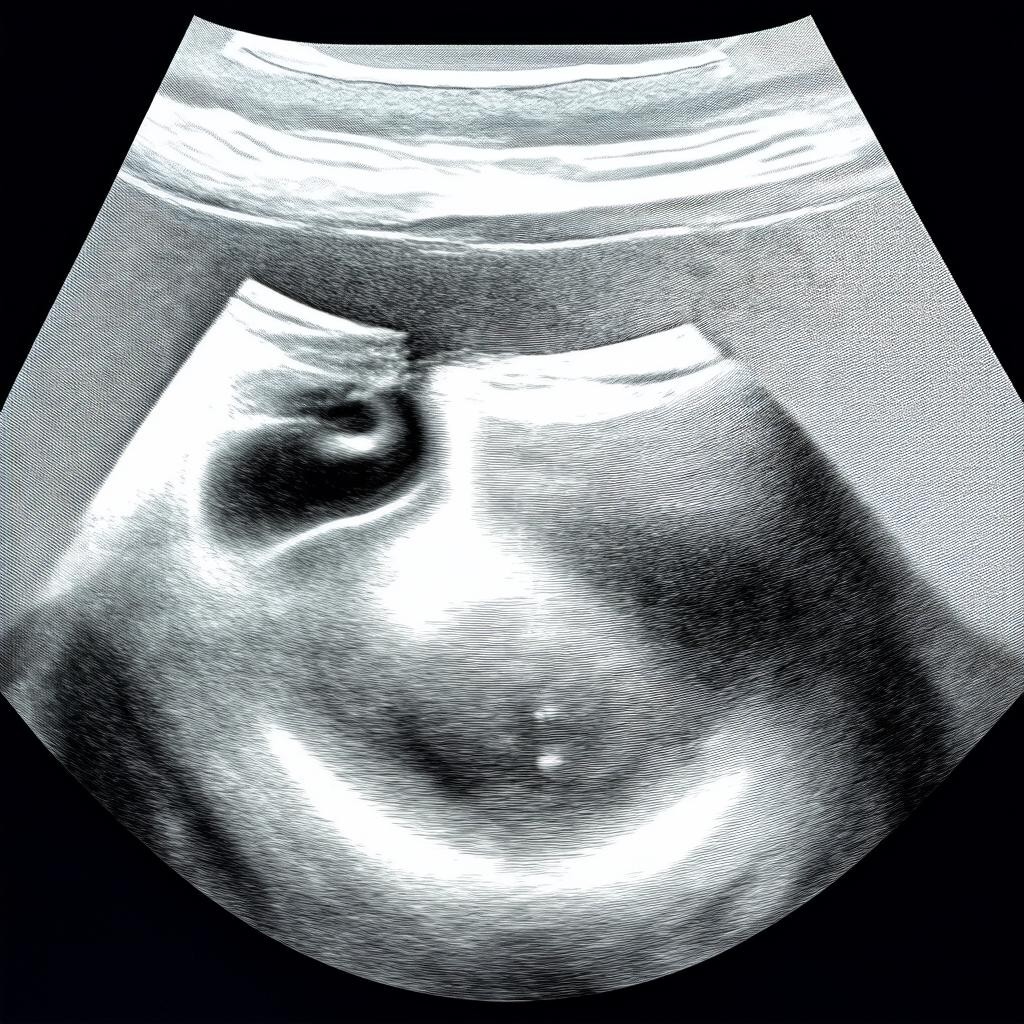

Отсутствие плодного яйца на УЗИ на 5 неделе беременности: причины и действия

Пятая неделя беременности — это период, когда большинство женщин только узнают о своем положении. На этом сроке плодное яйцо уже должно визуализироваться на УЗИ, но иногда его не обнаруживают. Это может вызвать тревогу у будущей мамы. Разберемся, почему так происходит и что делать в такой ситуации.